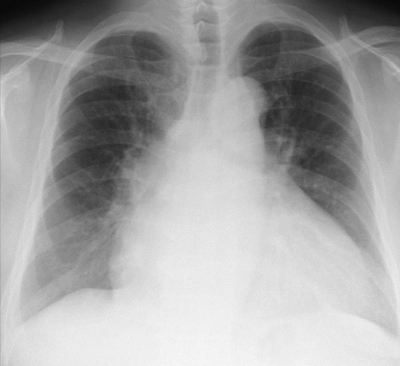

体温 36.4 ℃。脈拍 112/分、整。血圧 152/82 mmHg。呼吸数 20/分。SpO2 95 %(room air)。両下胸部にcoarse cracklesを聴取する。胸部エックス線写真を別に示す。心電図は洞性頻脈でST-T変化を認めない。心エコー図を別に示す。